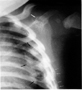

Fractura de escápula

Fractura de escápula (acromion) y de costillas: Este caso es evidente de maltrato, pues en la parte superior podemos ver una flecha blanca que señala una fractura del acromion, en la parte baja señalado con flechas blancas y negras fracturas de costillas. Es elocuente por la rareza de estas lesiones que este niño fue víctima de abuso.